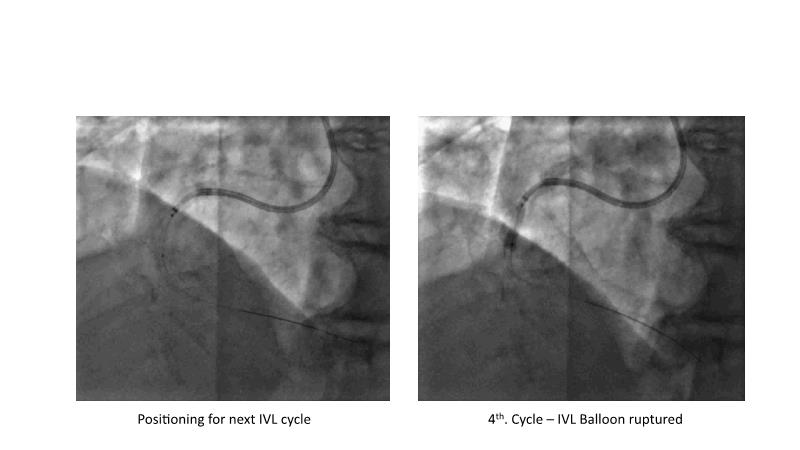

This session is recommended for you if you are seeking insights into the advantages of using IVUS imaging over visual assessment for better outcomes in left main bifurcation procedures. Discuss with experts the benefits of using RotaCUT in lesion preparation for left main bifurcation and explore the impact of high radial strength stents on the procedure's success.